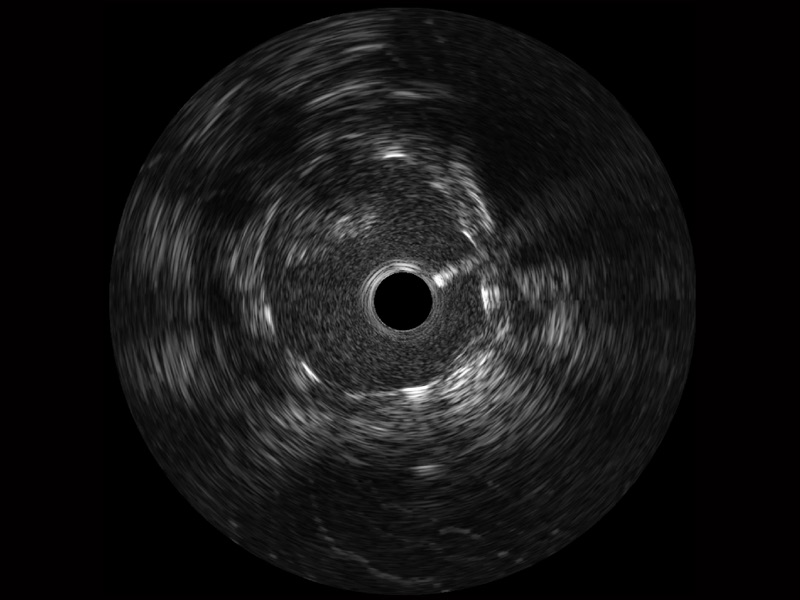

传统IVUS图像

对比传统IVUS导管成像,新葡的京集团8814检测站宽频IVUS图像的近场支架梁显影更细腻,远场中膜外血管仍清晰可辨,兼顾远中近,兼顾分辨力与穿透深度